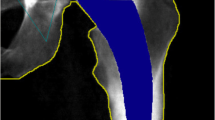

After the 3D bone surface was extracted, the model was then imported into the 3-Matic software package (Materialise, Leuven, Belgium), and a FE mesh of the pelvis was generated. We evaluated the Young’s modulus for every element of mesh using a power relationship developed by Keller et al. [17] for both trabecular and cortical bone. We imposed a Poisson ratio of 0.3 and Young’s modulus value of 17 GPa for the largest Hounsfield unit (HU) from the CT scan, which was in range with values obtained by Taddei et al. for the femur [18]. The development of the FE model along with the final inhomogeneous 3D reconstruction of the pelvis is shown in Fig. 1.

The defects along the acetabular rim were generated to fit the AAOS classification of minor type I segmental defects. A summary of how the FE model was generated in comparison to previously validated in vitro experiments is shown in Fig. 3. Using a U-shaped profile we created six defects by rotating the volume 60 degrees around the plane of the acetabular rim. The parametric volume, which was 20 mm in depth and width, was subtracted from the intact reconstructed pelvis. The defects were rounded at the edges to avoid false stress concentrations. The mean and standard deviation of the Young’s modulus for the bone removed to create each defect was calculated and compared using a 2-tailed Student t test. The acetabular cup position was identical to that described for the probabilistic finite element analysis. We then applied a 1600 N load that simulates one leg stance during fast walking to compute the von Mises stress distribution and contact surface area.

(1) FE model was previously validated by performing in vitro studies where a segmental defect was created along the superior rim of the acetabulum. CT scan of the pelvis was performed and imported into MIMICS, and the defect was created using a Boolean subtraction between the 3D model and the CAD volume. (2) Cementless press-fit acetabular cup was inserted into the acetabulum. (3) FE analysis was used to evaluate contact surface, cup insertion force, and stress distribution with different loading profiles. Five other segmental defects were created along the acetabular rim and evaluated for the same properties to understand the implications of the location of a segmental rim defect